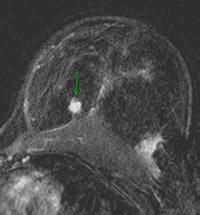

| Contrast-enhanced breast MRI (subtracted image three minutes after contrast medium injection). Patient with a diagnosis of invasive ductal carcinoma (ultrasound-guided biopsies). At surgery, no cancer was found. Ultrasound examination after surgery was unable to detect the lesion. At MRI, the lesion was well depicted (inner quadrants, deep location). Image courtesy of Dr. Anne Tardivon. |